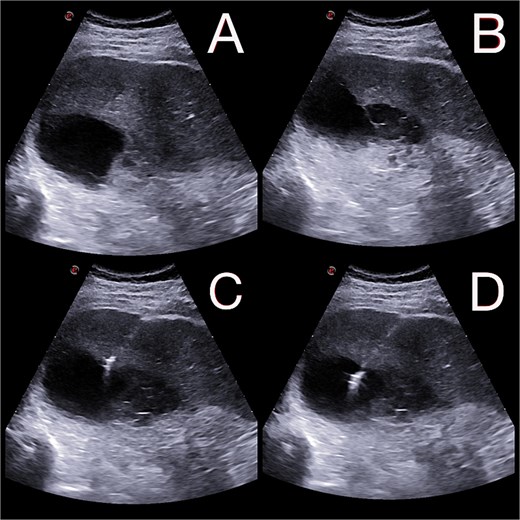

On postoperative day 14, the patient remained febrile. Computed tomography revealed a secondary abscess in segment VII (Fig. 2), which was successfully managed by percutaneous drainage under ultrasound guidance (Fig. 3). The regimen was subsequently switched to intravenous linezolid 600 mg twice daily, combined with antifungal therapy. The drains were gradually removed by postoperative day 30, while intravenous therapy continued until day 35. The patient was discharged on day 37.

(A and B) Abdominal ultrasound depicting a 9 × 5 cm abscess in segment VII. (C and D) Percutaneous drainage performed with placement of a 10 Fr catheter under ultrasound guidance.